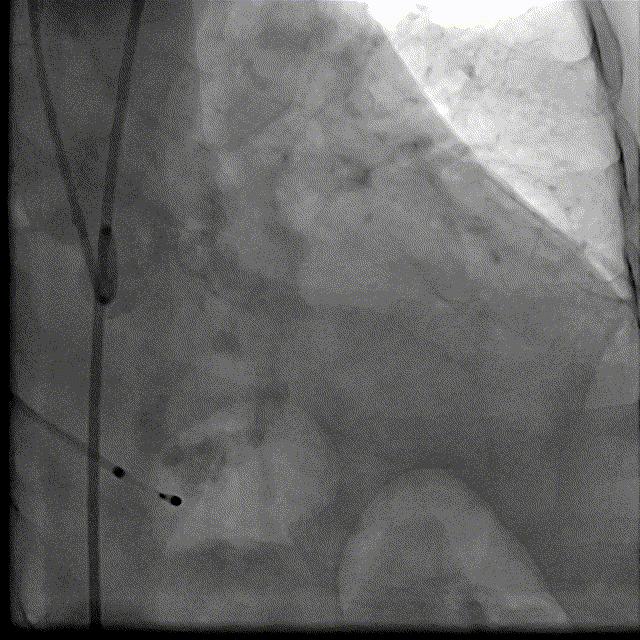

根部造影DSA